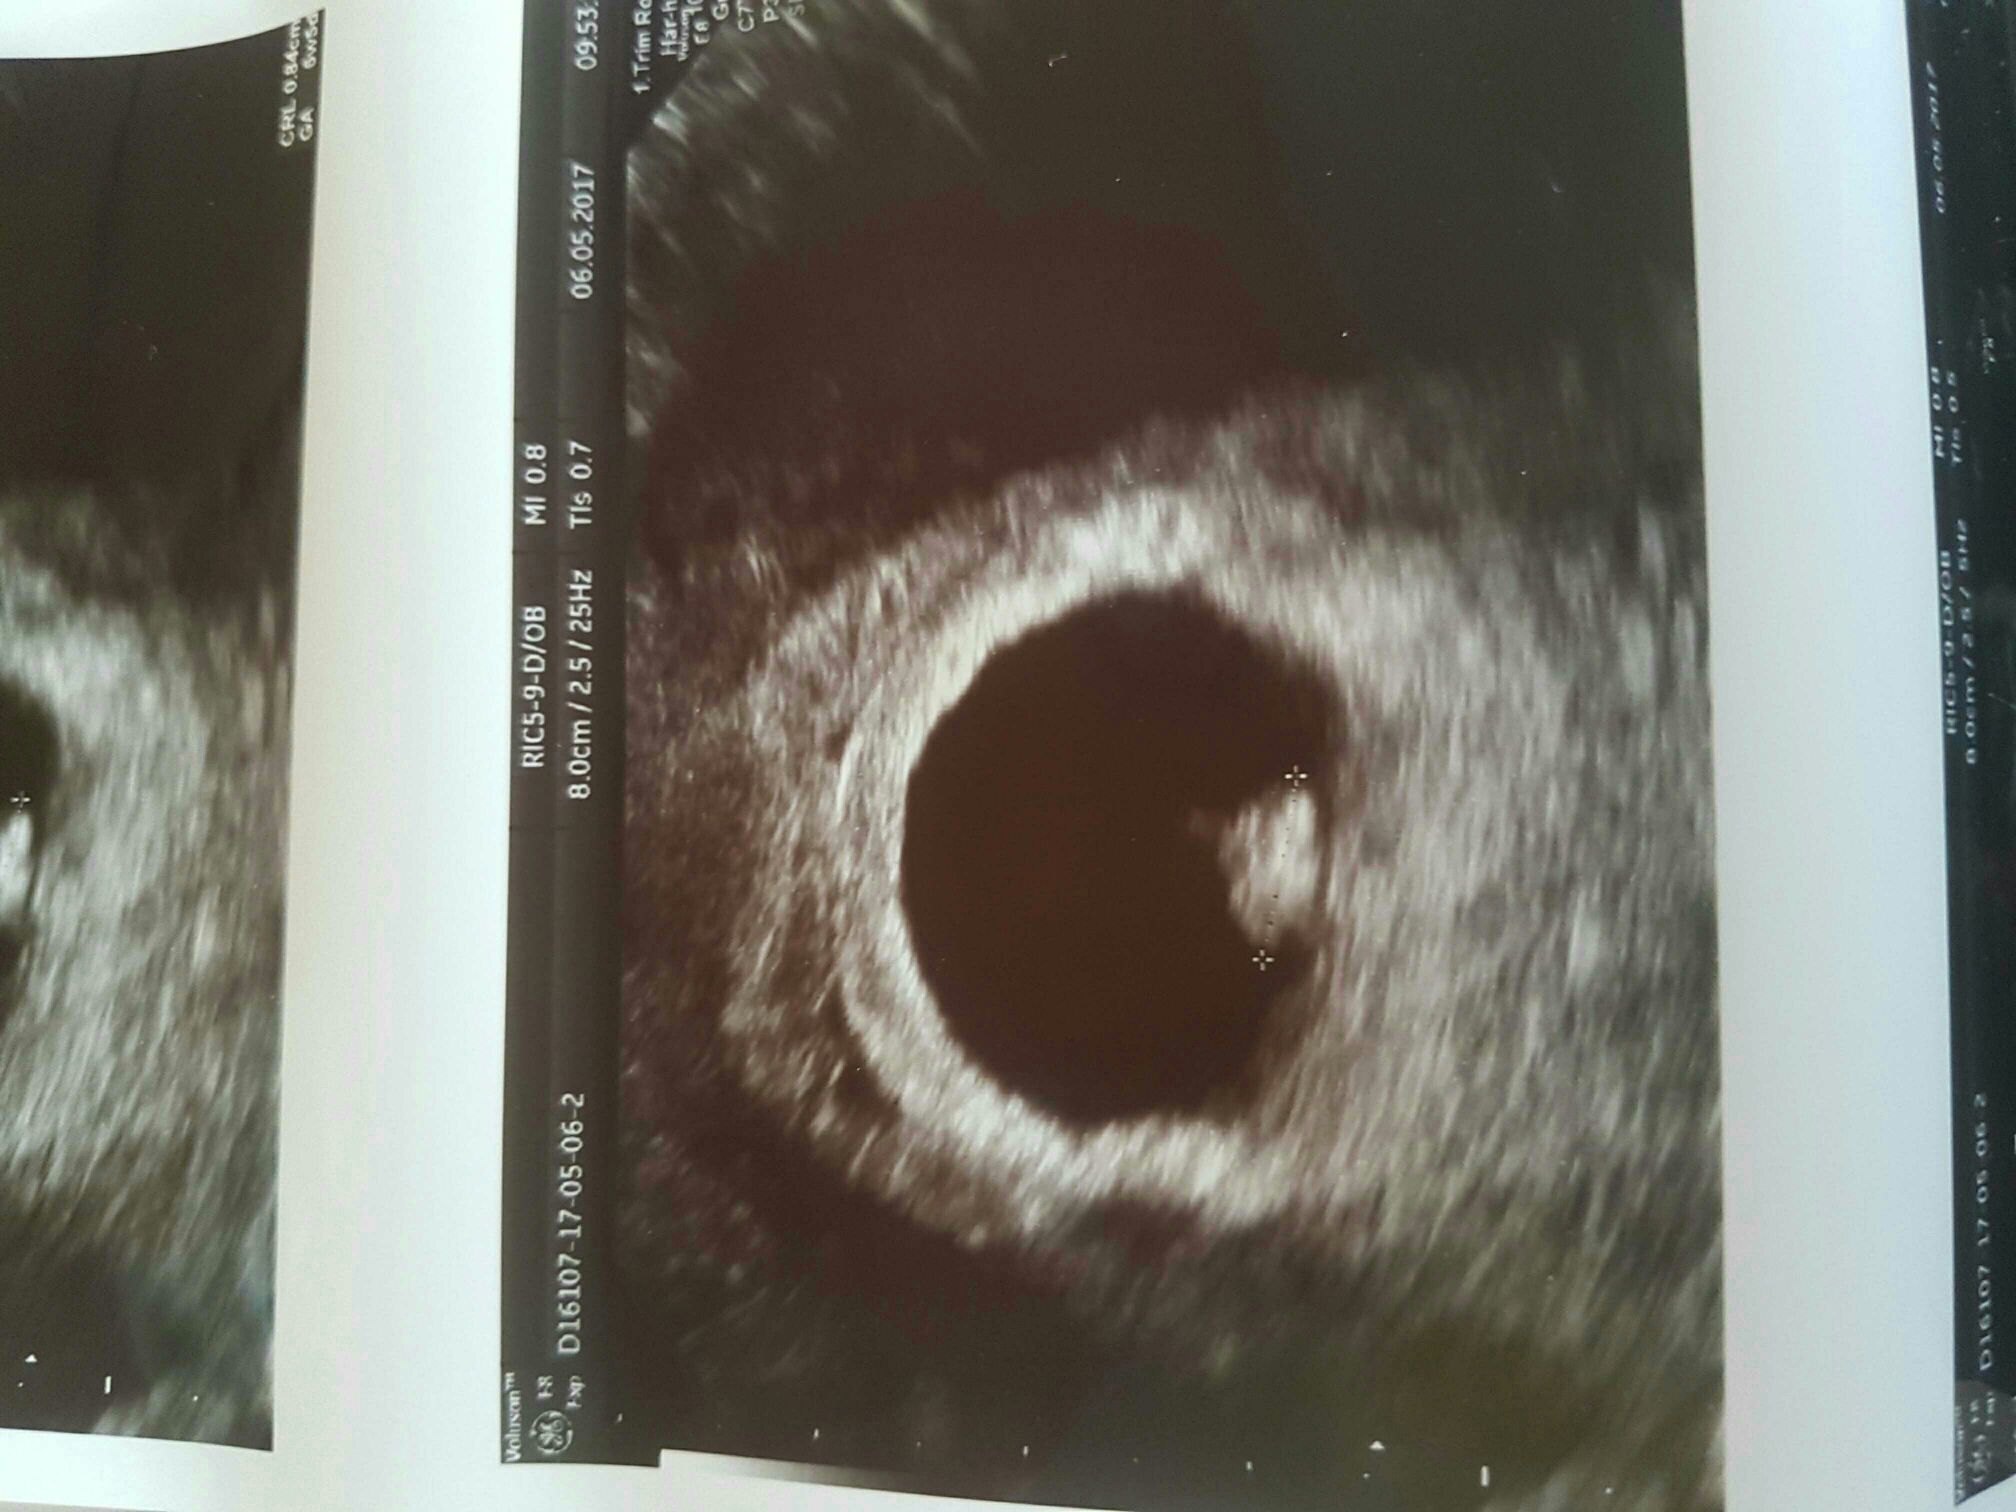

Cześć dziewczyny [emoji4]

Wróciłam właśnie od gina.

Było piękne i zdrowe serduszko[emoji173]

Termin teoretycznie na 28.12

1494062785-aaaaaa.jpeg